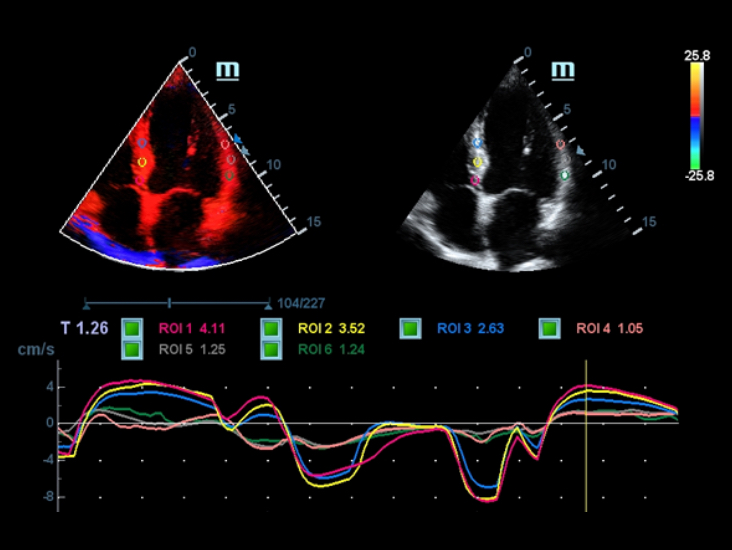

Smart Track

Smart Track biedt snelle en intelligente optimalisatie voor vasculaire beeldvorming met slechts ├®├®n druk op de knop. Het optimaliseert het kleuren-, power- en PW-spectrum met zelftracking en reduceert het aantal tijdrovende stappen. De workflow voor vasculair onderzoek wordt daarmee vereenvoudigd met een optimale weergave.